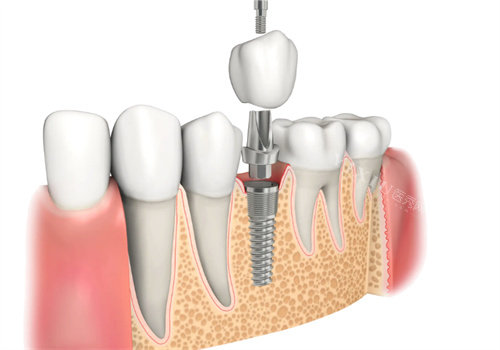

韩国8plant种植体是韩国HOOWON EDI公司的代表性产品,近年来在牙齿种植领域逐渐受到关注。它以其独特的技术和设计,为患者提供了高品质的牙齿修复解决方案。本文将从多个方面深入解析韩国8plant种植体的优缺点,帮助您更好地了解这一产品。

韩国8plant种植体采用ASTM认证的四级钛合金材料,这种材料具有优异的生物相容性,能够有效减少人体对异物的排斥反应,确保种植体与骨骼长期稳定结合。

8plant种植体采用了SLA(喷砂酸蚀刻)表面处理技术,通过在种植体表面形成微观粗糙度,促进骨细胞的快速附着与增生。这种技术显著缩短了骨整合时间,提高了种植体的初期稳定性。

8plant种植体支持数字辅助设计与制造(DAP系统),能够根据患者的具体口腔状况提供个性化的治疗方案。这种个性化设计不仅提高了种植体的适配性,还优化了治疗结果。

8plant种植体拥有多种型号(如BX、TX、EX、NX和SX系列),每种型号都有其独特的设计理念和适用范围,能够满足不同患者的需求。

8plant种植体外观精致,能够与周围牙齿融为一体,修复后美观自然。

韩国8plant种植体凭借其高质量的材料、可靠的表面处理技术、丰富的型号选择以及良好的性价比,在口腔种植领域展现出了显著的优势。虽然存在价格相对较高、市场有名有待提高等问题,但其在生物相容性、稳定性和耐用性等方面的优势使其成为许多患者的理想选择。